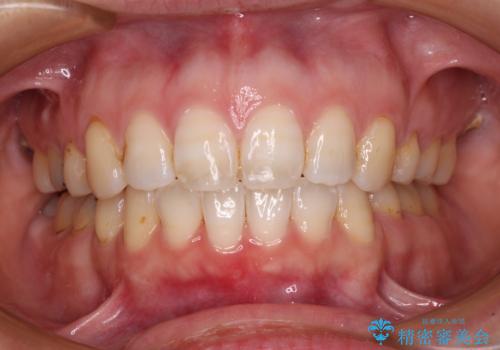

積極的に前歯を牽引したことで、口元の閉じにくさは顕著に改善され、横顔のシルエットが大幅に変化しました。

- 口元の閉じにくさと、前歯のでこぼこの歯並びを気にして来院された患者様です。

口元を積極的に引っ込めるために、上下左右の小臼歯計4本を抜歯することとしました。

セオリーでは第一小臼歯を抜歯しますが、上下右側は第二小臼歯に銀歯が装着されているため、第二小臼歯を抜歯することとしました。

上下正中を左右対称に揃えるため、アンカースクリューや補助装置を使用しながら口元を下げていくこととしました。